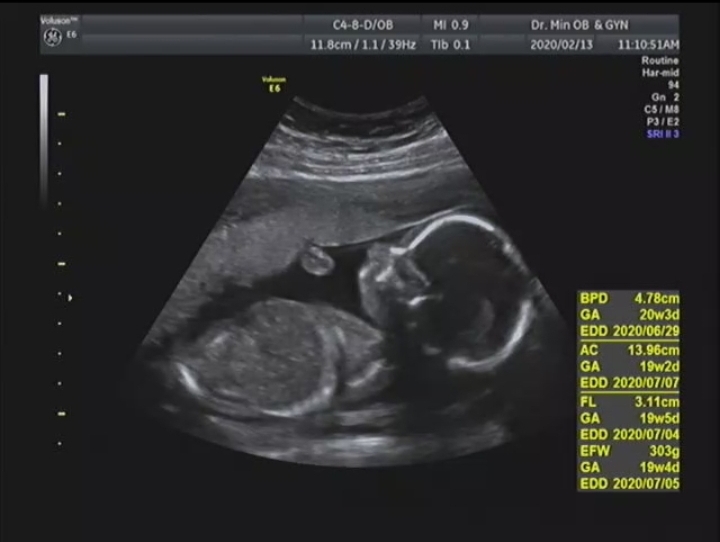

태아 초음파 용어 : BPD AC FL EFW GA EDD

벌써 19주인 저!! 꺄!! 사실 12주까지는 진짜 시간 안간다고 느꼈는데 그때부터는 슝슝 가더라구요. 19주부...